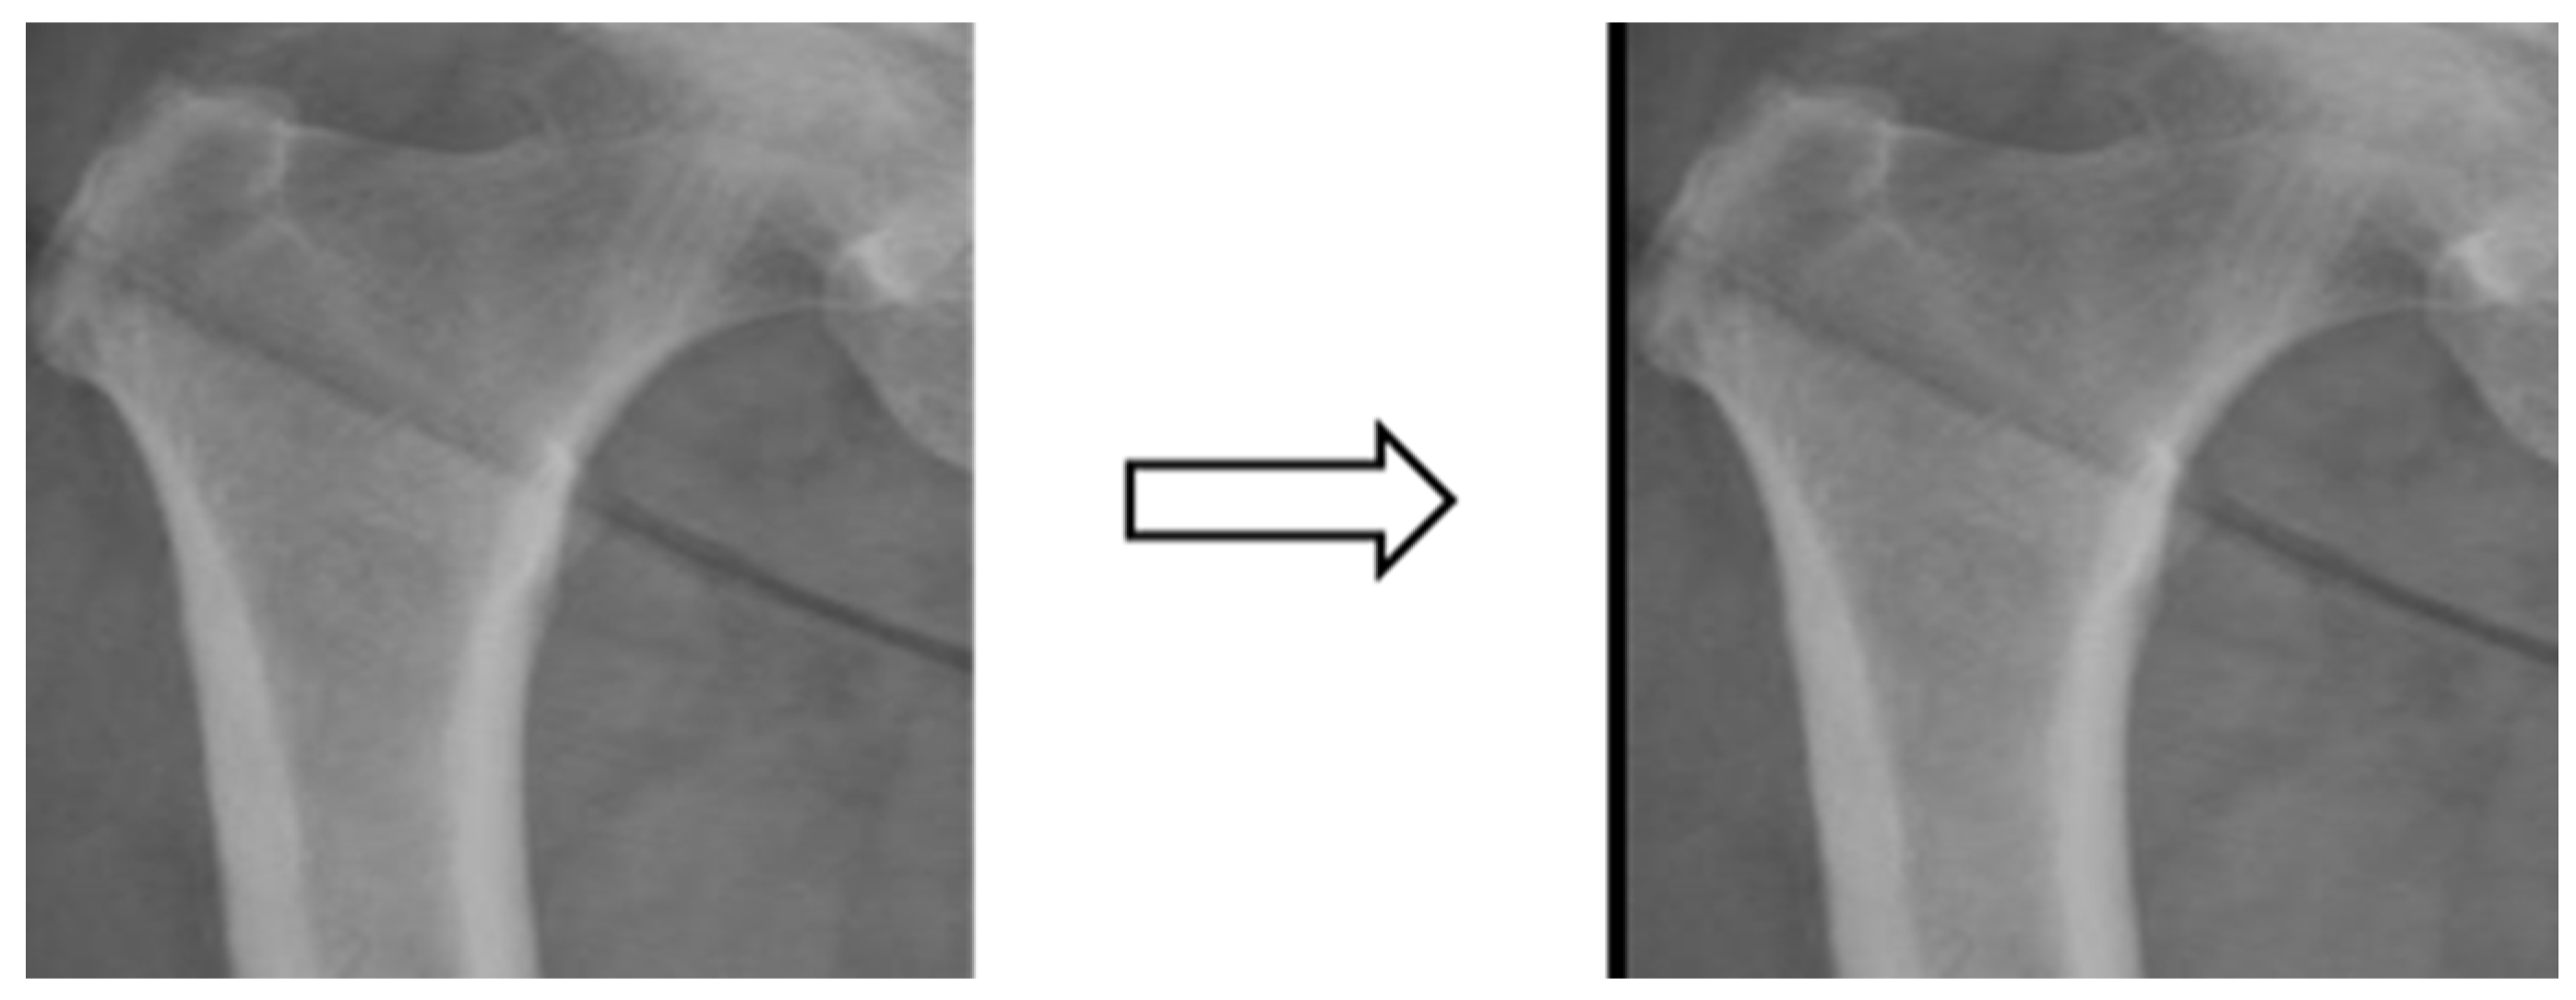

3.3.2. Image Segmentation

In this study, four parts of the image labeled X-ray images were used in image segmentation by feeding them into U-Net and U-Net++ models for training, and the bit depth of the four parts of the image was converted from the original 24 bits to 8 bits before the model training. The reason for choosing to use U-Net and U-Net++ is that their model structure is simpler, they do not need to spend a lot of time filtering out the remaining noise in the medical images, and they are less likely to form overfits for a small number of image datasets. The binary segmentation prediction results obtained after training the models of U-Net and U-Net++ are shown in Figure 3 below.

Figure 3.

Image segmentation.